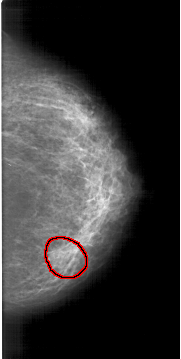

A_1298_1.RIGHT_CC

RIGHT_CC LINES 6451 PIXELS_PER_LINE 3241 BITS_PER_PIXEL 12 RESOLUTION 43.5 OVERLAY

FILE: A_1298_1.RIGHT_CC.OVERLAY

TOTAL_ABNORMALITIES 1

ABNORMALITY 1

LESION_TYPE MASS SHAPE ROUND MARGINS OBSCURED

ASSESSMENT 4

SUBTLETY 3

PATHOLOGY BENIGN

TOTAL_OUTLINES 1

BOUNDARY